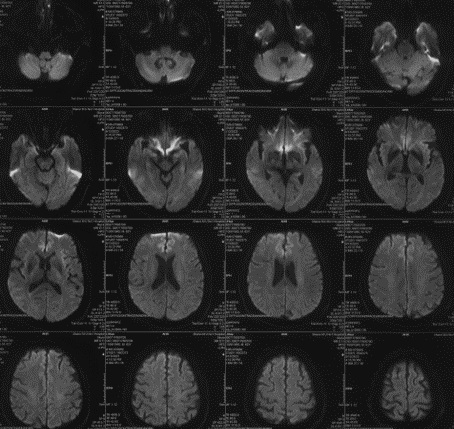

辅助检查(头颅核磁)

波科支架怎么样径技-弓上病例大赏|第210期·右侧颈内动脉球囊扩张术+支架植入术_https://www.jmylbn.com_新闻资讯_第9张

波科支架怎么样径技-弓上病例大赏|第210期·右侧颈内动脉球囊扩张术+支架植入术_https://www.jmylbn.com_新闻资讯_第10张